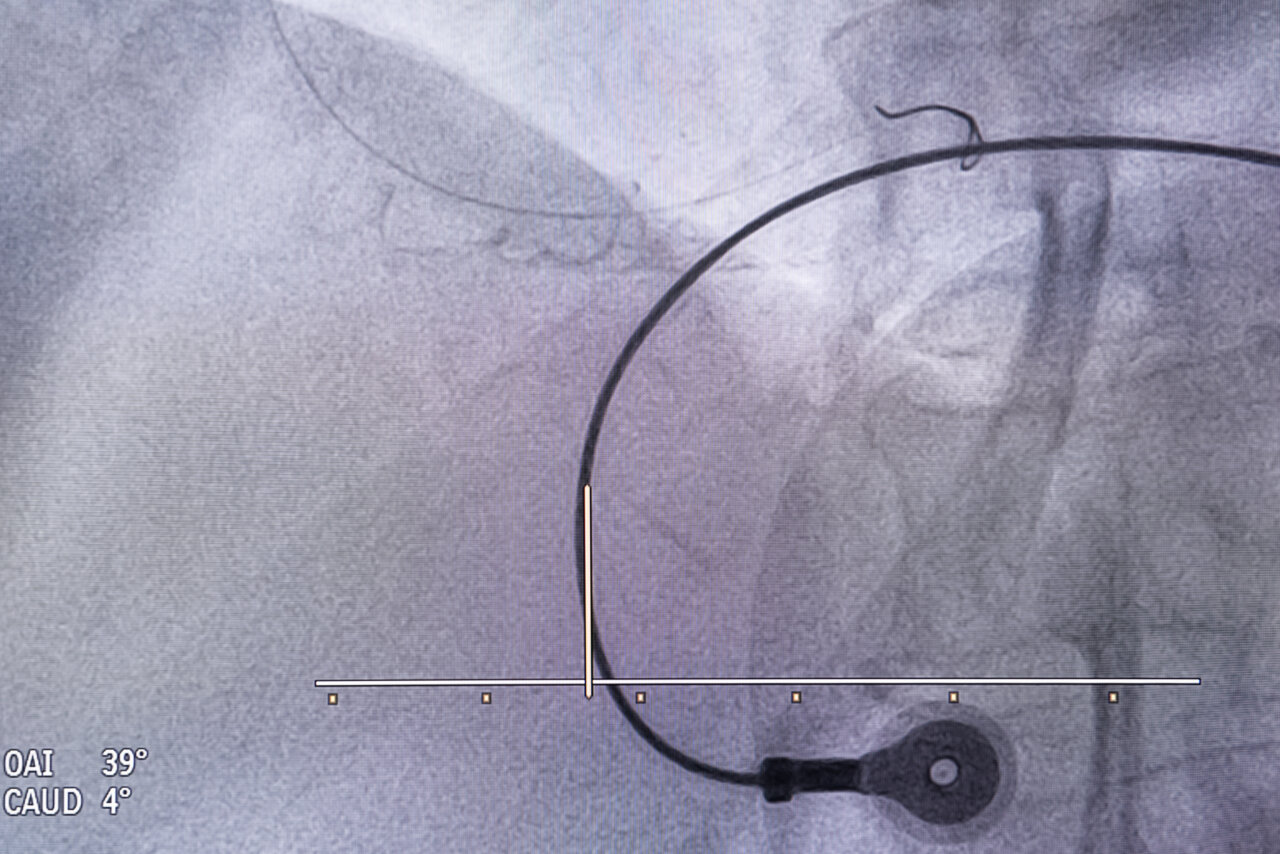

—¿En qué consiste el cateterismo que se realiza en la sala de hemodinámica?

—Del 97 al 98% de los cateterismos se inician con una pequeña incisión en la arteria radial, muy próxima a la mano, a través de la cual se introducen catéteres (tubos muy finos de plástico flexible) que llegarán al corazón, guiados por la imagen de rayos X y con un contraste, lo que nos permite saber en cada momento dónde estamos, identificar el problema y seleccionar la secuencia del tratamiento. Es decir, si vamos a dilatar primero, con un globo, para abrir la arteria y luego poner un stent. Si vemos que hay mucho coágulo tenemos catéteres que extraen parte del trombo para facilitar la colocación del stent. La guía por rayos X y el contraste nos permite saber dónde está la lesión, qué longitud tiene y si la coronaria es más o menos gruesa. En función de esas variables seleccionamos el balón y el stent que se le va a colocar al paciente. Tenemos materiales de diferentes tamaños y medidas que cubren la inmensa mayoría de las posibilidades.

—Una vez colocado el stent y abierta la arteria, con el mismo contraste observamos que el resultado haya sido óptimo. Entonces suspendemos el cateterismo, se retira el catéter y se coloca en el sitio en donde se ha pinchado una pulserita que comprime la artería para que no sangre, durante de 3 a 6 horas, momento en el que sustituye por una tirita o un vendaje mínimo.